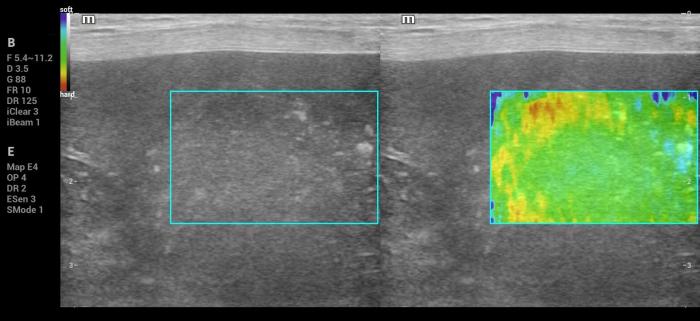

Además de la medición cuantitativa de la velocidad de la onda de corte expresada en metros por segundo (m/s), el sistema Natural Touch Elastography® (Mindray MX7) dispone de una función complementaria de representación cualitativa y semicuantitativa de la rigidez tisular (Figura1-4). Esta herramienta permite asignar valores numéricos y porcentajes relativos al grado de dureza o blandura del tejido evaluado y facilita la comparación visual y numérica entre diferentes regiones de interés dentro de un mismo órgano, incluyendo la relación entre una lesión focal y el parénquima esplénico adyacente.

De acuerdo con la documentación técnica del fabricante, esta funcionalidad se basa en el análisis de la respuesta tisular al impulso acústico y en algoritmos de seguimiento por radiofrecuencia, lo que contribuye a una evaluación intraorgánica más precisa. Si bien estos valores no sustituyen las mediciones cuantitativas en m/s ni cuentan con puntos de corte validados para la diferenciación diagnóstica, su utilización aporta información complementaria útil para la interpretación clínica de los hallazgos elastográficos, especialmente cuando se integra con la evaluación en modo B y Doppler.

Hallazgos elastográficos (Natural Touch Elastography®): El análisis mediante NTE evidenció una rigidez baja, comparable al parénquima esplénico normal, sin zonas internas de aumento marcado de velocidad (Figura 15-16). Las mediciones fueron consistentes, con buena calidad técnica y sin artefactos significativos.